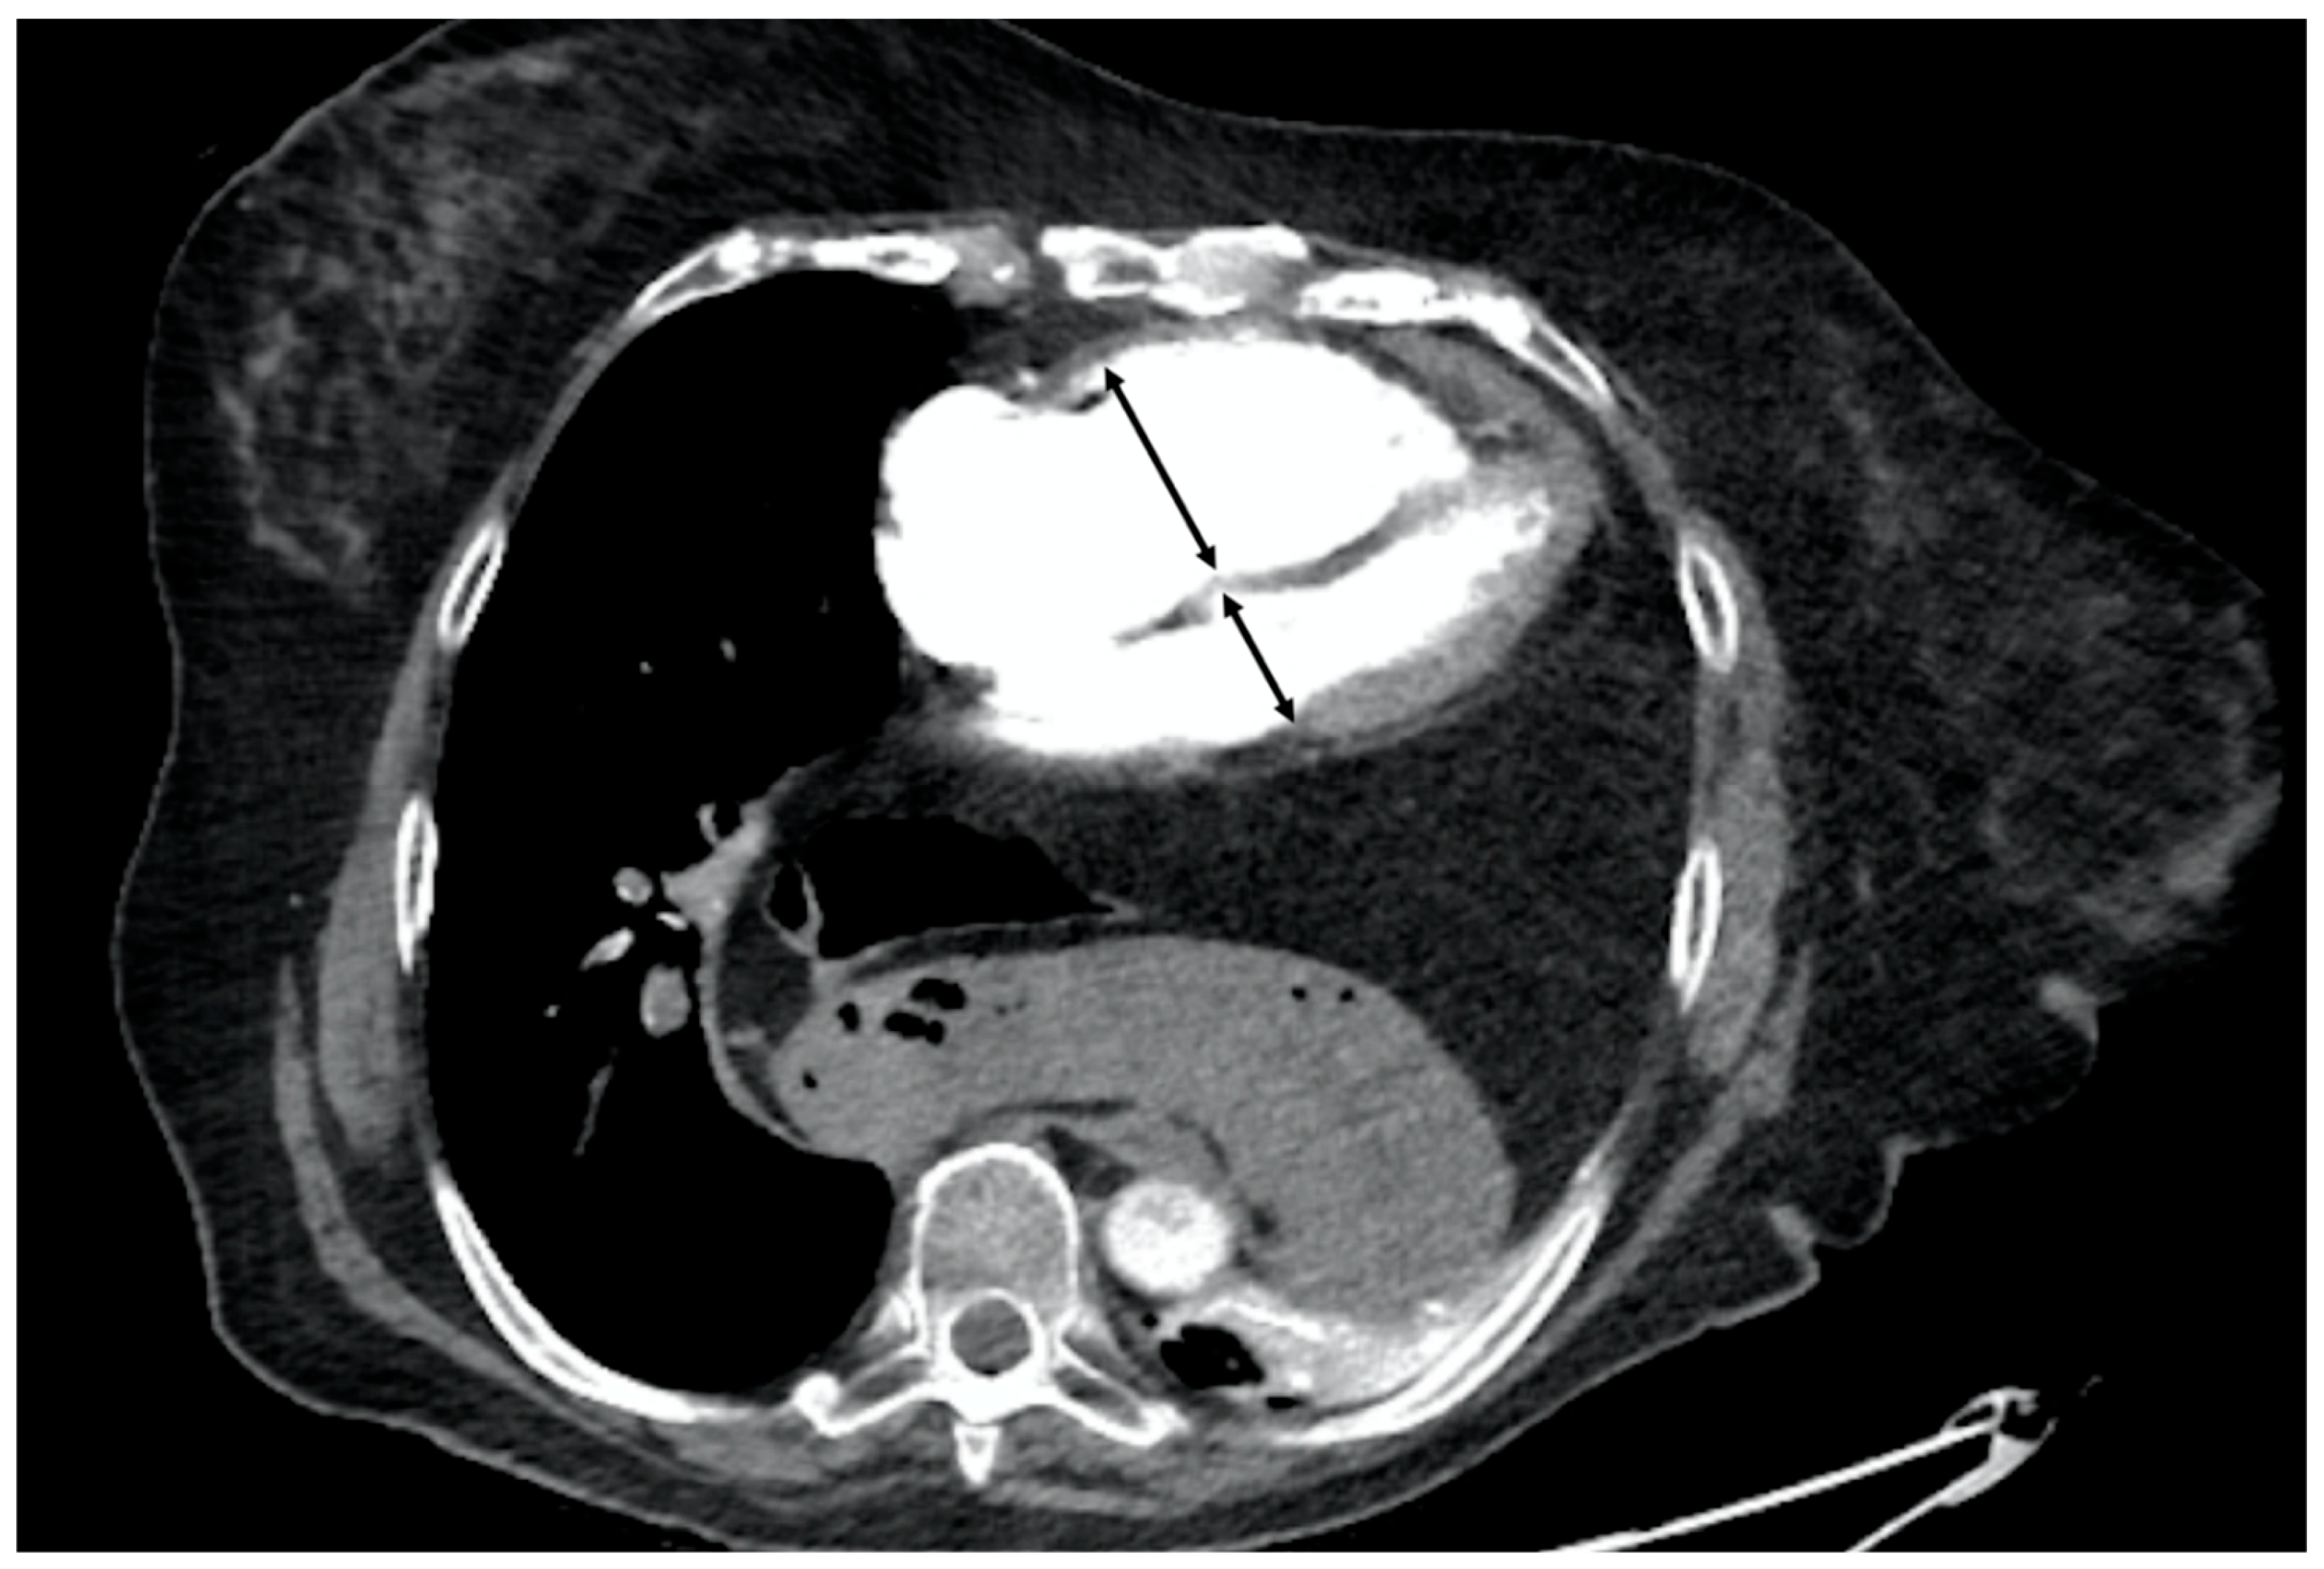

Further studies underscore the importance of multispectral CT [21,22,23,24,25]. These systems capture data at two energy levels, which facilitates the differentiation of tissues with varying attenuation levels. This is particularly beneficial for substances like calcium and iodine, which have high attenuation. The differentiated materials are presented through their decomposition, and each material can be calculated using an absorption algorithm. Different materials will exhibit distinct behaviours under various energy levels, allowing for more effective differentiation than with a single energy spectrum. This capability enables the creation of "iodine maps" (Figure 2), which specifically illustrate the presence of iodine in different slices. Dual-energy CTPA can thus enhance the detection of pulmonary embolisms and aid in stratifying their severity [24]. On these maps, the distribution of iodine is directly proportional to blood volume, thus enabling the definition of pulmonary blood volume (PBV) maps. Defects distal to emboli are not commonly detected, as they are more frequent (82-95%) in occlusive emboli compared to non-occlusive ones (6-9%). As such, they are considered an indicator of severity, and numerous studies have demonstrated that a higher number and size of defects in the PBV correlate with adverse findings, such as increased pulmonary arterial obstruction indices and right ventricular (RV) dysfunction, measured by an RV/left ventricular (LV) diameter ratio >1 [24]. However, Im et al. [23] found that only the RV/LV ratio was a higher risk factor for all-cause mortality at 30 days, and not quantitative PBV measurement, in their propensity score matching comparing multispectral CT with conventional CT. More recently, Lee et al. [22] published findings on the quantitative analysis of pulmonary perfusion, comparing the relative PBV value (%PBV) and normalised PBV (PBVm) by pulmonary density, and discovered a significant correlation between PBVm and sPESI.

Figure 2. 89 years old woman diagnosed with chronic pulmonary thromboembolism. A and C. Axial and sagittal CT angiography (MIP recon), respectively, showing severe narrowing in the superior segmental artery of the left lower lobe (white arrow) as secualea of PE. B. Fusion image of CT angiography and color-coded iodine density showing wedge-shaped perfusion defects in the middle lobe, lingula, and left lower lobe, with the latter corresponding to the findings in images A and C. D. SPECT-CT fusion image showing wedge-shaped perfusion defects similar to those obtained with Dual Energy CT (B).